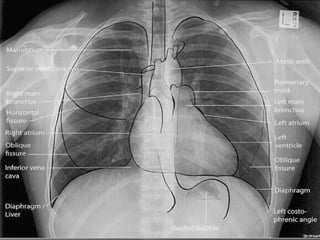

 10. Mediastinum

 Check for

 Cardiomegaly

 Mediastinal and

Hilar contours

for hilar masses

 11. Diaphragms

 Check sharpness of

borders

 Right is normally

higher than left

 Check for free air,

gastric bubble,

pleural effusions